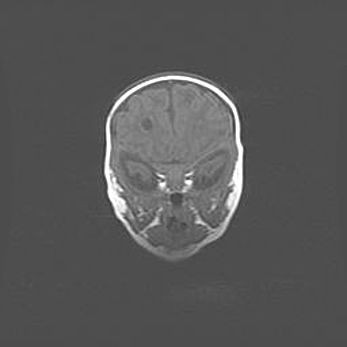

Множественные кисты обоих полушарий головного мозга, наибольшая из них в правой затылочной области. Ассиметричная атрофическая гидроцефалия.

Возраст: 7 месяцев

Вес: 5660 г

Пол: мужской

Окружность головы: 41,5 см

Срок гестации: 28-29 недель

Кисты головного мозга развиваются в результате многоочаговых некрозов вещества мозга и возникают вследствие перенесенной перинатальной инфекции, менингитов, энцефалитов, асфиксии, родовой травмы, расстройств мозгового кровообращения различного генеза. Образованию кист в веществе головного мозга плодов и новорожденных способствуют такие факторы, как высокое содержание в нем воды, недостаточная (или отсутствие) миелинизация и слабая астроглиальная реакция на повреждение.

Кисты могут сочетаться с гидроцефалией и другими поражениями головного мозга.